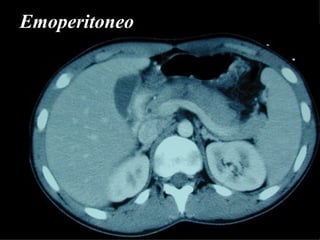

Emoperitoneo

DAMAGE CONTROL Controllo dell’emorragia e delle lesioni contaminate mediante abbondanti lavaggi, packing pelvici , suture provvisorie delle ferite e delle cavità addominali e successivo intervento chirurgico dopo 6 – 12 ore.